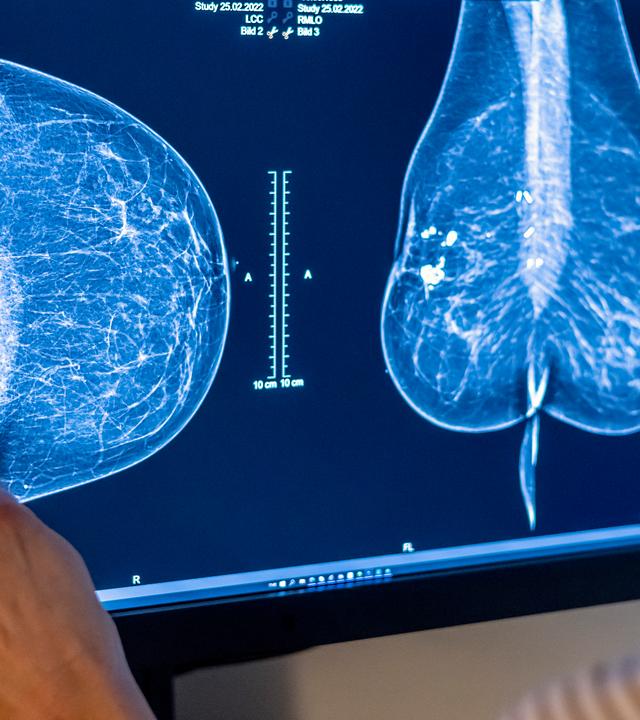

Aufnahmen einer Mammografie

Ab Juli sollen Frauen bis zum Alter von 75 Jahren zur Brustkrebs Früherkennung eingeladen werden. Doch das Mammografie-Screening steht seit langem in der Kritik. Sinnvoll oder nicht?

Ab Juli 2024 wird die Brustkrebsfrüherkennung für Frauen bis zum Alter von 75 Jahren als "Kassenleistung“ angeboten. Das bedeutet fünf Jahre länger Früherkennung als bisher. Das Institut für Qualität und Wirtschaftlichkeit im Gesundheitswesen IQWiG hat eine Empfehlung ausgesprochen, da sich die Lebenserwartung von Frauen in den letzten 30 Jahren entsprechend erhöht hat. Kritiker bemängeln, dass Frauen, die am Screening teilnehmen, meist nicht gut über Risiken und Nutzen des Screenings aufgeklärt sind. Umfangreiche Studien haben ergeben, dass der Nutzen durch das Screening sehr gering ist.